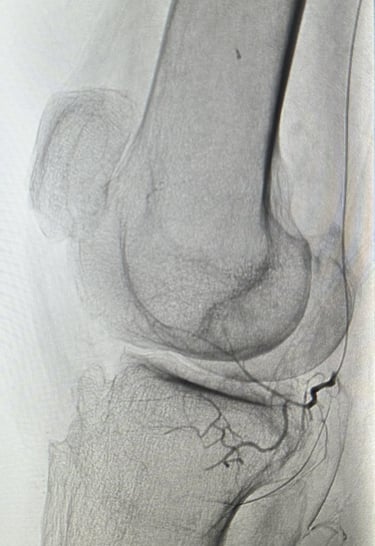

Une artériographie par injection de produit de contraste iodé est réalisée. Elle permet la cartographie des artères à destinée du genou pour repérer les zones d'hypervascularisation et de synovite, qui sont le témoin d'une inflammation locale de la gaine articulaire du genou (la synoviale).

L'objectif de la procédure est de boucher (=emboliser) ces artères anormalement développées qui alimentent les zones inflammatoires de l'articulation, c'est à dire les zones de synovite, pour diminuer l'apport vasculaire et arrêter le cycle de l'inflammation.